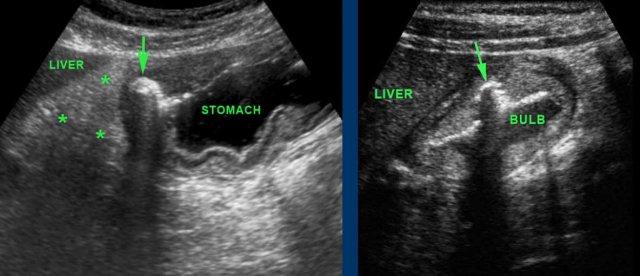

The left image shows a gastric ulcer (arrow).

Lưu ý sự mất cấu trúc lớp ở thành dạ dày mặt bụng và lớp mỡ viêm (dấu hoa thị) đại diện cho mạc nối và mạc treo ruột, đang cố gắng bao bọc vùng sắp thủng từ vết loét dạ dày xuyên sâu này.

Hình bên phải cho thấy một ổ loét (mũi tên) ở thành bụng của hành tá tràng chứa đầy dịch.